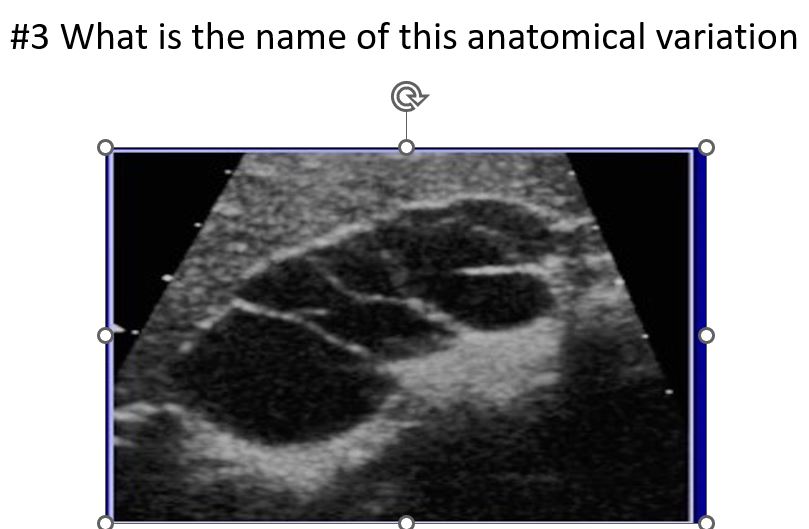

Septations within Gallbladder

phrygian cap

sigmoid gallbladder or junctional folds